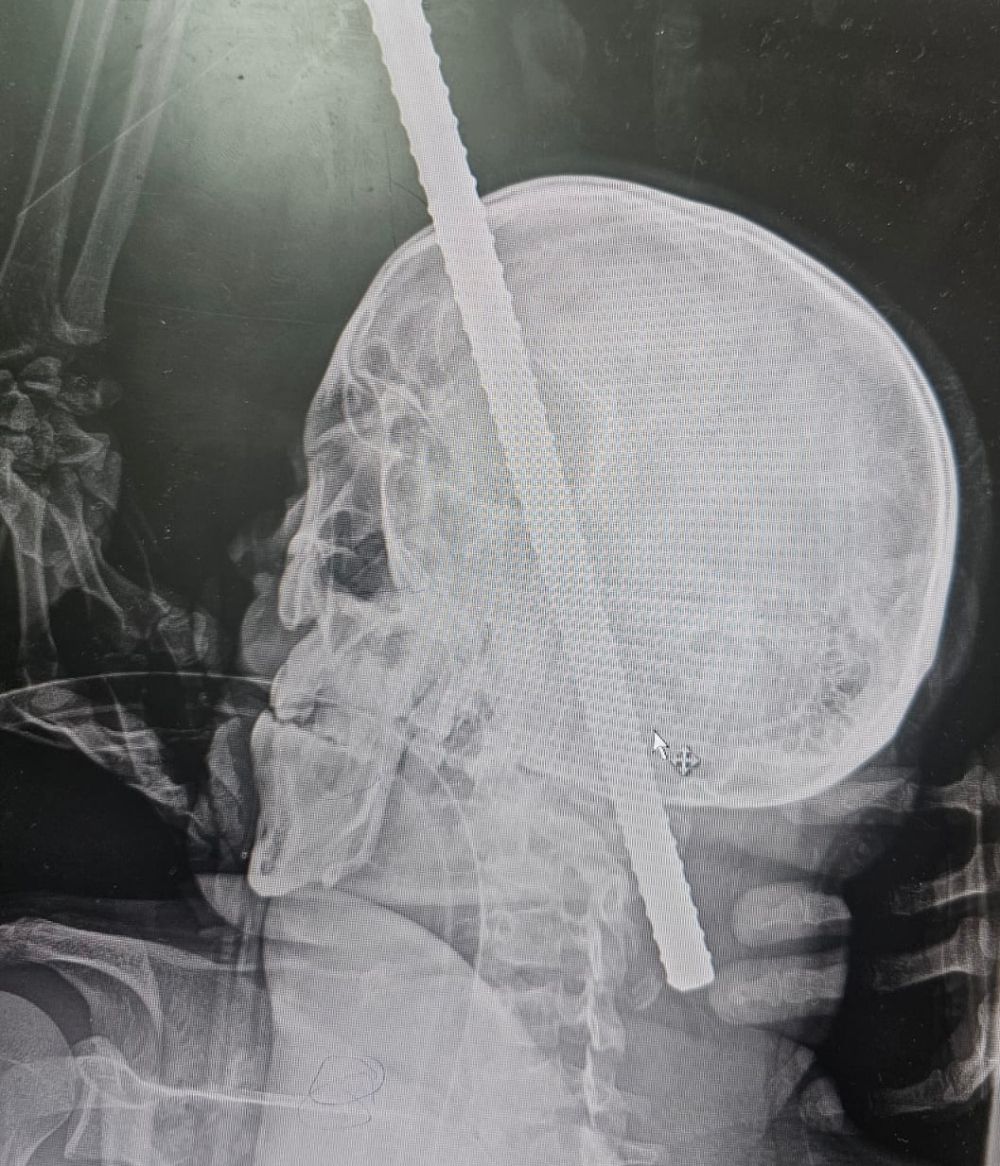

وأوضح تجمع المدينة المنورة الصحي أن المصاب وصل إلى طوارئ المستشفى الرئيسي وهو في حالة حرجة، فاقدًا للبصر في عينه اليسرى ويعاني من نزيف حاد وآلام شديدة، نتيجة اختراق جسم حديدي بطول 43 سم وعرض 14 ملم لتجويف العين اليسرى مرورًا بالفك العلوي، وقاع الجمجمة، والفقرة العنقية الأولى، وصولًا إلى قناة الحبل الشوكي والجزء الخلفي من العمود الفقري.

وأظهرت الفحوصات والأشعة المقطعية مدى تعقيد الإصابة وخطورة الجسم المعدني الذي اقترب من جذع الدماغ وأجزاء حيوية أخرى.